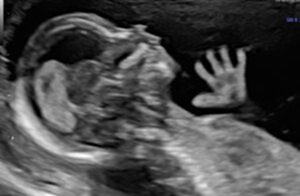

2/3/4D pretecho

Een 3D/4D HD live echo is alsof je een kijkje neemt in de buik. Bij Baby’s World is het mogelijk om een vroege 3/4D pretecho te maken tussen 13 en 19 weken zwangerschap. Vanaf 20 – 34 weken zwangerschap is het mogelijk om het gezicht van jouw kindje goed in beeld te krijgen met een 3/4D pretecho. De beste periode is tussen de 24 en 30 weken zwangerschap.